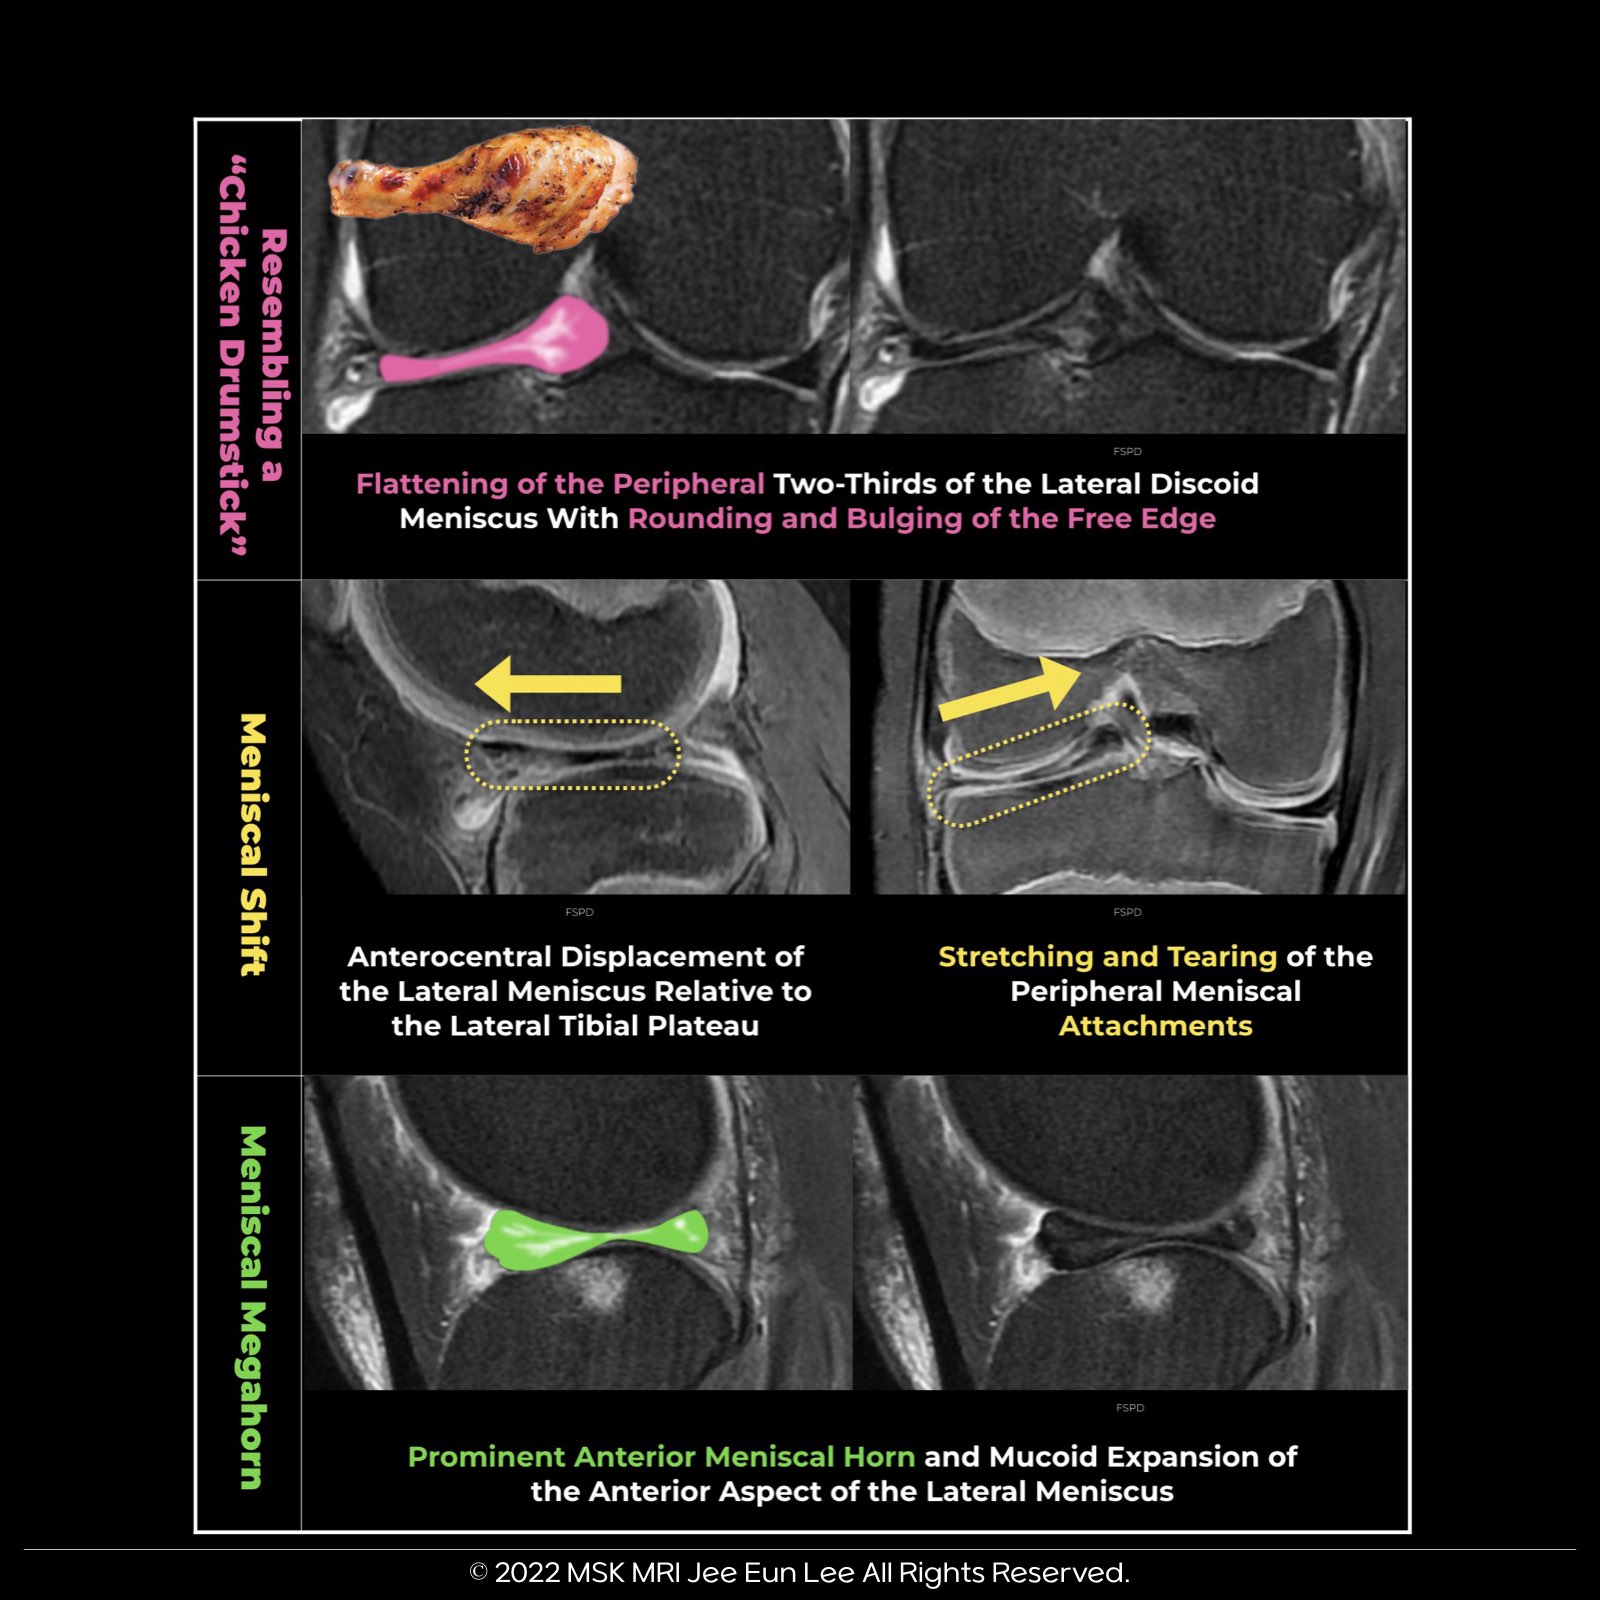

Meniscal and Shape Deformation in Discoid Lateral Meniscus:

- Meniscal Deformation: Indicates peripheral detachment through abnormal infolding, buckling, and shifting.

- Shape Deformation: Signals early instability with surface changes, meniscal shifts, and development of meniscal megahorns. Important imaging signs include:

- Chicken Drumstick Appearance:

On MRI, the meniscus may bulge at the free edge and flatten elsewhere, resembling a chicken drumstick in the coronal plane, often with an increased intrameniscal signal. - Pseudo–Bucket-Handle Tear:

Refers to a centrally flipped discoid meniscus (DM) or middle segment into the intercondylar recess without a longitudinal tear, indicating underlying hypermobility and peripheral rim instability. - Posterior Megahorn:

Results from progressive anterior capsular detachment leading to instability. Conversely, an anterior megahorn indicates a Wrisberg-type DM with absent posterior attachments.